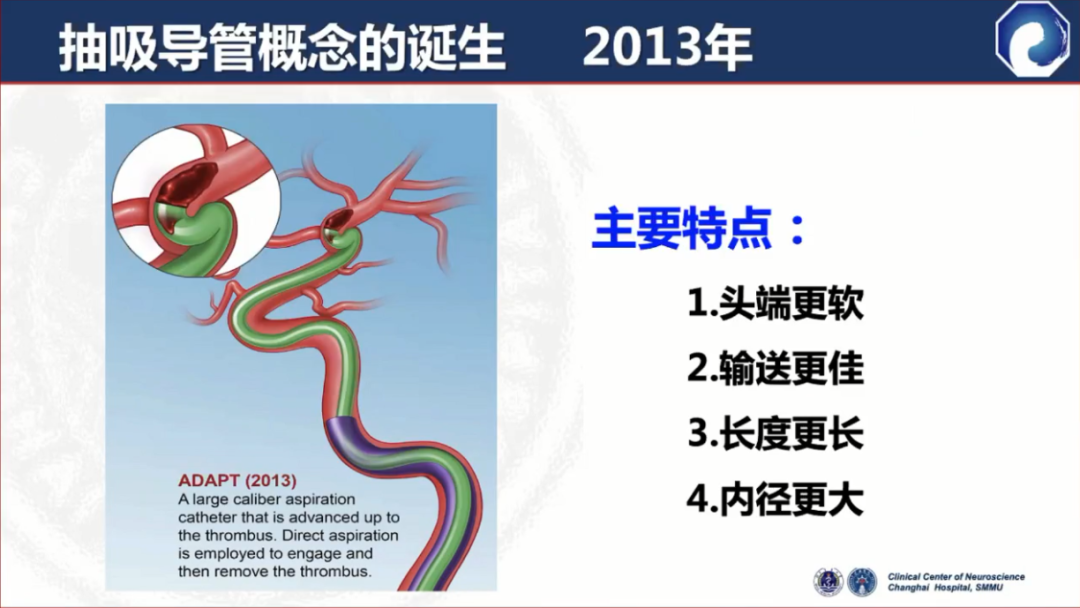

随着取栓技术的发展,抽吸导管的概念诞生。主要特点:头端更软、输送更佳、长度更长、内径更大